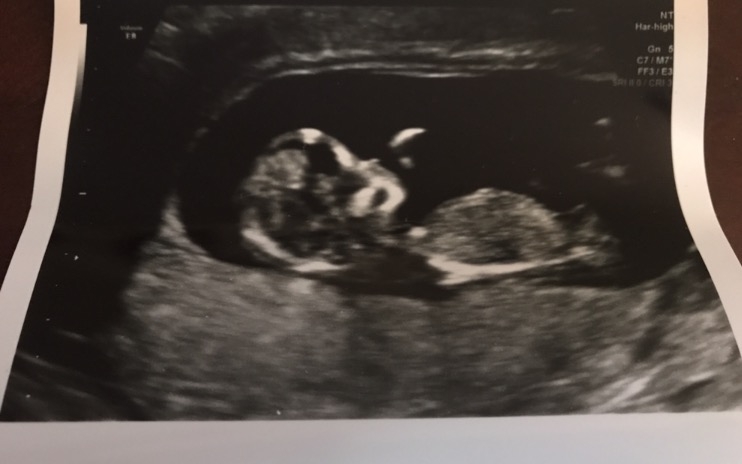

• Thanks for the positive vibes ladies! I am posting the NT scan photo on two threads because I am so excited.

This is little cutie was looking perfect and everything was on target! S/he was sucking its thumb the last couple scans, but at least DH got to see it this time!

The nasal bone and the back of the next measured right on target (which was great because Down's syndrome runs in my family).

I got stuck FOUR times to get one vial of blood. I wasn't even dehydrated since I had to drink a ton of water right before the scan for a full bladder, so I don't know what the issue was. I have always been a hard stick, but this was ridiculous! I will get those results back in about a week!

The 20 week anatomy scan is scheduled for November 30th!